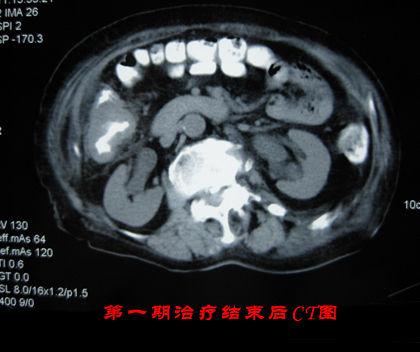

考虑到患者前期接受过放化疗的治疗,并且其身体产生了严重的放化疗副作用,因此我院专家特给予患者李某WB-1无创全身热疗系统的治疗方案,通过这套治疗方案的治疗效果,以期达到帮助患者李某彻底清除肿瘤组织的目的。在李某接受一个疗程的治疗效果后,专家通过CT图发现李某体内的肿瘤组织见明显缩小,遂给李某安排第二期的肿瘤治疗。在李某接受我院WB-1无创全身热疗系统治疗三个疗程后李某的病情完全得到了控制,其病情未出现反复,身体各项技能也均以恢复健康。